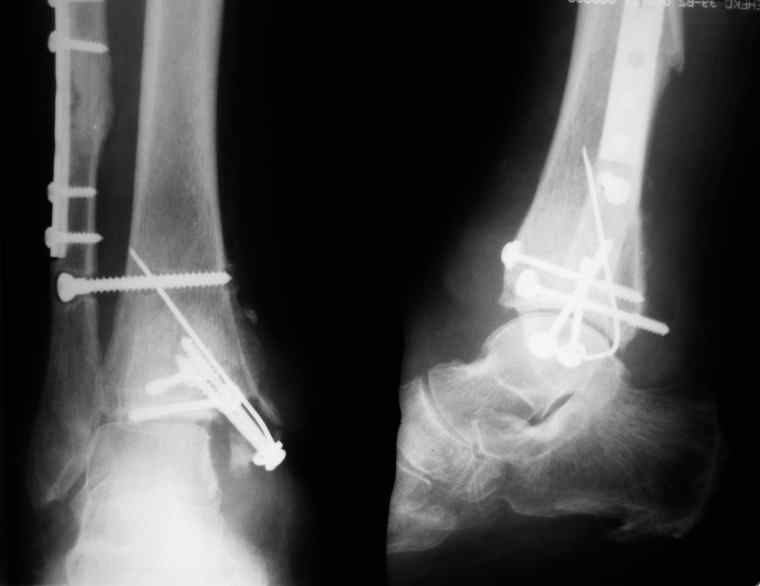

Уважаемые коллеги нужна помощь в определении тактики лечения: Больная Р.,1952 года рождения получила травму 18 августа 2007 года.

31 августа 2007 года была оперирована в другой области по поводу DS Закрытого двухлодыжечного перелома правой голени с подвывихом стопы кнаружи , кзади. Разрыв дистального межберцового синдесмоза. Перелом заднего края большеберцовой кости справа. Поступила в наше отделение со швами ,с некрозом медиальной поверхности правого голеностопного сустава. Проведено : снятие швов , антибиотики , некрэктомия с последующей кожной пластикой .Заживление 20 декабря 2007 года ,выписана из стационара . 3 марта 2008 года поступает с гиперемией , отек , флюктуацией. В настоящее время имеется рана по медиальной поверхности правой голени ,отеки и гиперемия сохраняется .Наша тактика:1) снятия воспалительного процесса, 2) удаление металлоконструкции, 3) выполнения артродеза правого голеностопного сустава.

Алексей20 15 Март 2008, 14:03

Не очень удачный вариант остеосинтеза: сохранен подвывих стопы, синдесмоз не достаточно репонирован. Думаю, в данном случае у пациента д-з: остеоартрит правого голеностопного сустава, послеоперационный остеомиелит правой голени. Предлагаю тактику: одномоментно выполнить удаление металлоконструкции, хирургическую обработку очага остеомиелита, резекцию голеностопного сустава, артродез аппаратом. Другие методы лечения не привидут к купированию гнойного процесса. Так как полость сустава в настоящее время имеет вид пиогенной капсулы, в которой будет поддерживаться гнойный процесс даже после заживления свища, с последующим его открытием и опорожнением гноя.